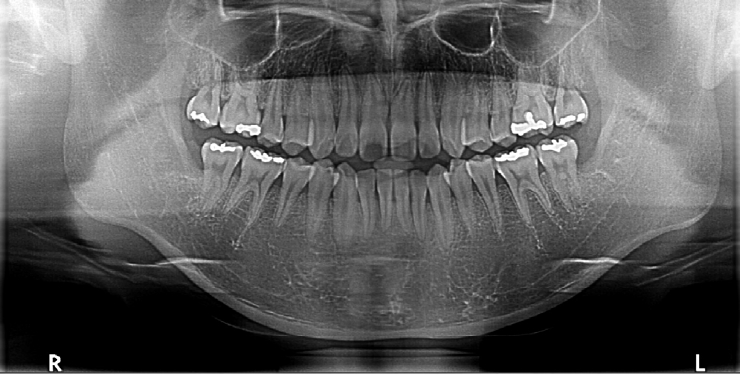

At the follow-up visit for suture removal, the extraction sites showed normal healing, and the patient reported no symptoms or complications (Fig. 4).